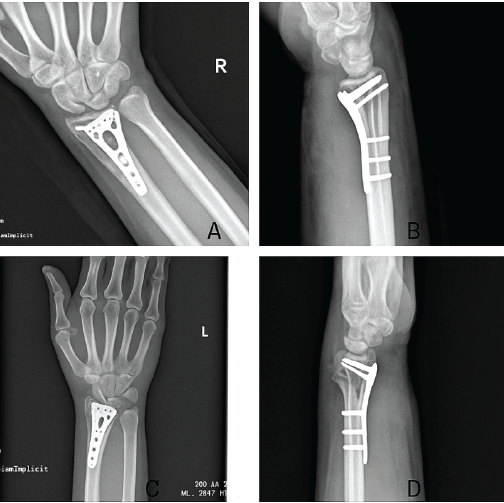

Radiographs confirmed complete bony union with proper implant positioning and anatomical alignment in both wrists (Fig. 6a, b, c, d). Functionally, the patient achieved elbow flexion from 0° to 130°, wrist flexion and extension of 60° and 60°, respectively, and full pronation and supination of 80° each (Fig. 7). He had successfully returned to his occupation as a laborer.

Figure 6: 6-month follow-up X-rays showing bony union of right wrist fracture in anteroposterior (a) and lateral (b) view, and left wrist fracture in anteroposterior (c) and lateral (d) view.